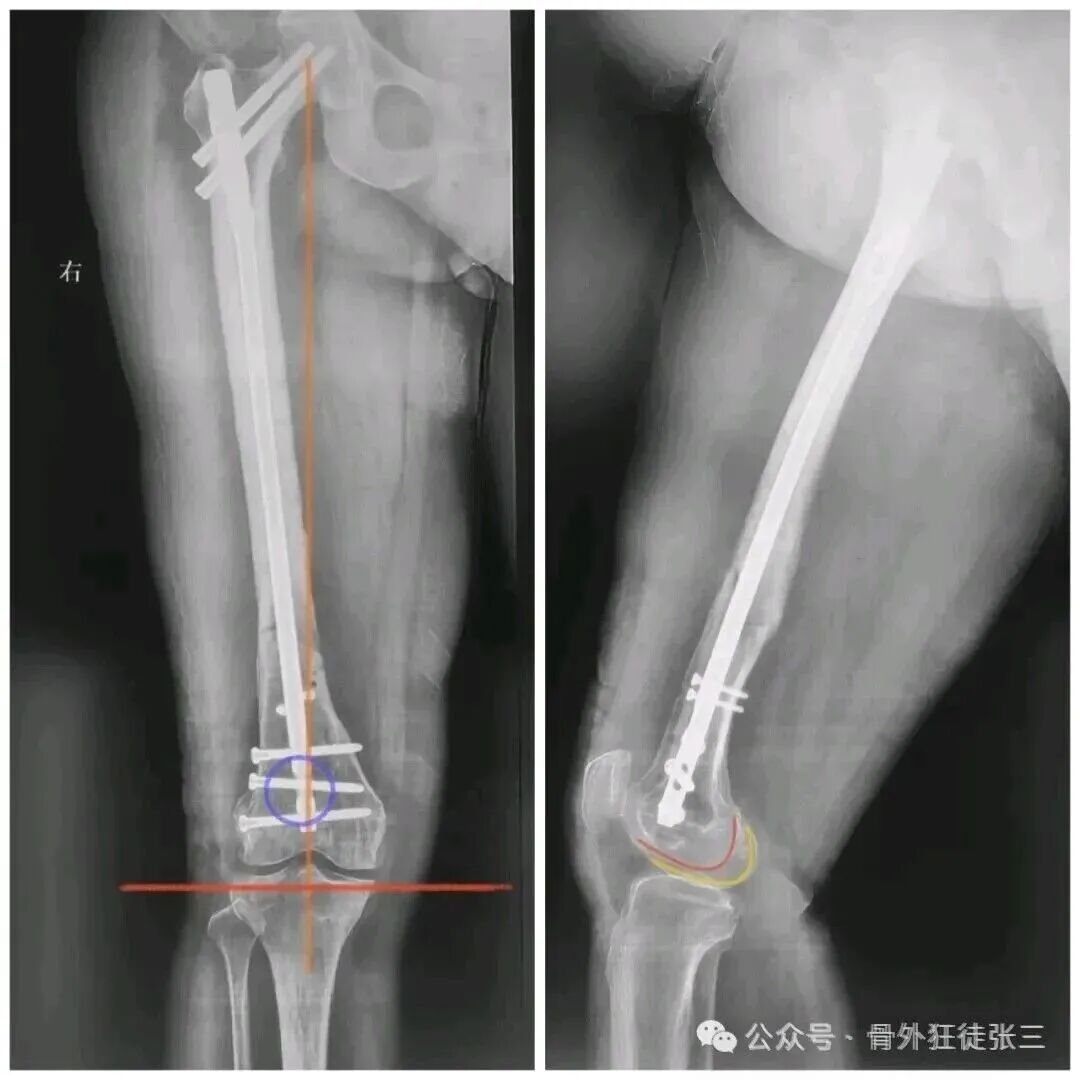

我们给予翻修

1,顺行髓内钉,头颈模式

2,全长保护,

3,最粗,够长

术后5个月完全愈合

这样全长保护

转子下,股骨颈或者股骨远端再骨折的概率

是不是非常小

几乎不会再出现?

这个患者术后14个月取了髓内钉